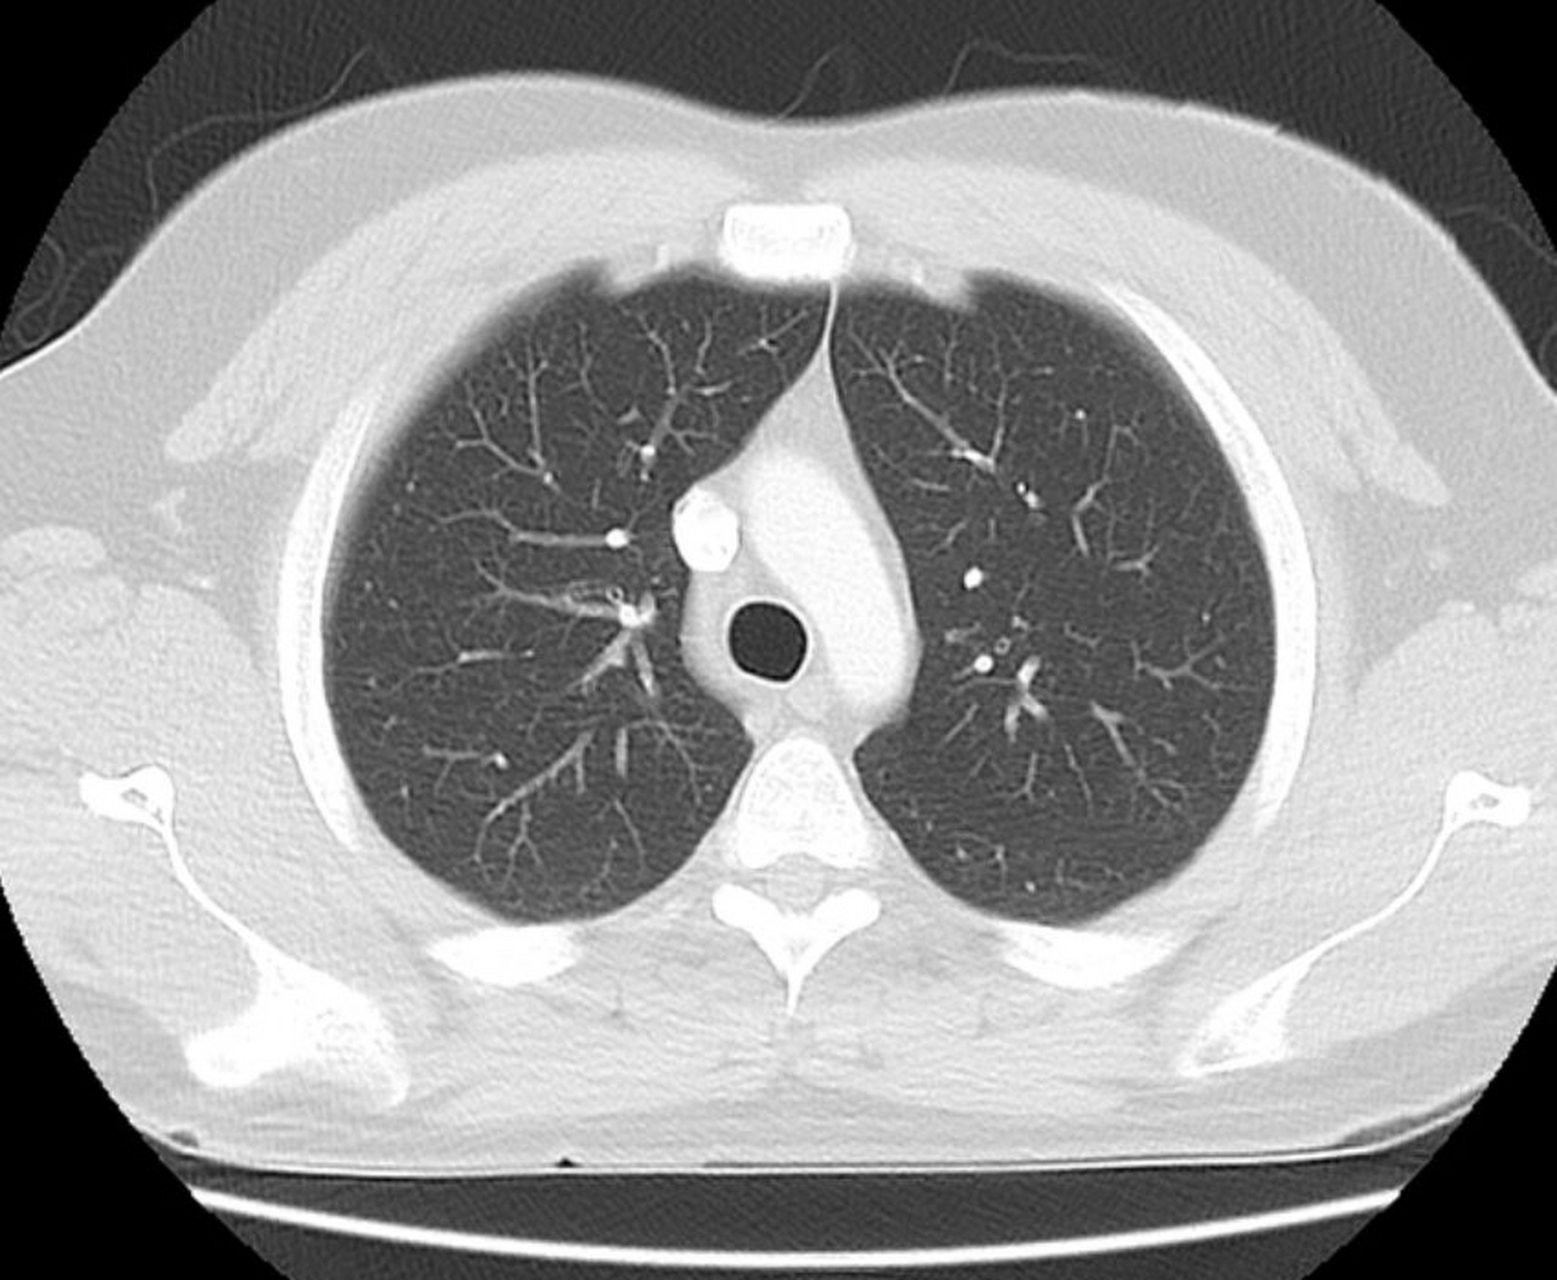

ct肺纹理增多

双肺纹理增多 影像显示肺部血管和支气管纹理较正常更为密集,可能与

肺ct报告上提示 肺纹理增多,增多 代表着什么

1,纹理增粗 肺部纹理增粗往往提示支气管及其周围组织存在慢性炎症

肺部ct肺ctct胸膜增厚怎么看工业肺ctct显示肺部陈旧病变肺纹理 ct